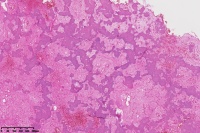

右胫骨内组织,单纯性骨囊肿?

性别

男

年龄

12岁

临床诊断

内生性软骨瘤?骨囊肿?

标本名称

右胫骨内组织

图2